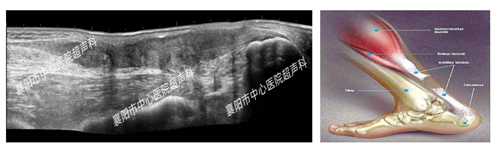

1、肌腱损伤的评估

(图中为篮球起跳过猛时导致的跟腱断裂)